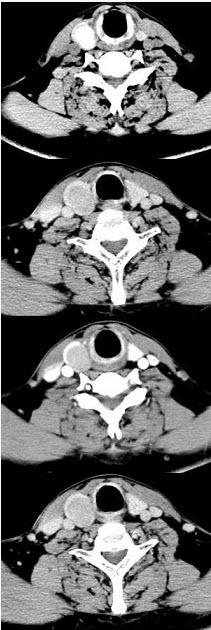

男,43岁,右颈部扪及一包块,CT如图所示,应诊断为()。

A、甲状腺腺瘤

B、甲状腺腺癌

C、结节性甲状腺肿

D、甲状腺原发淋巴瘤

E、甲状腺转移癌

A